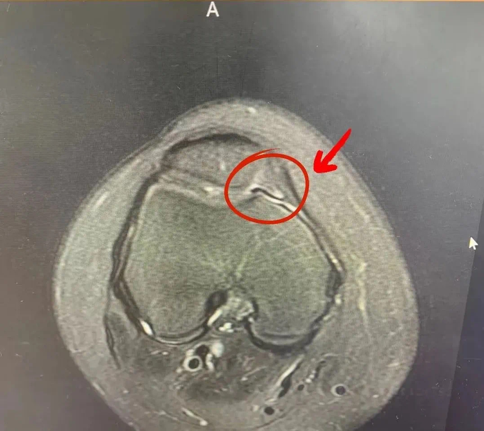

说起这个疾病我们需要了解什么是滑膜及膝关节滑膜皱襞,滑膜是被覆于关节囊内面的结缔组织膜,局部滑膜组织折叠后形成的结构称为滑膜皱襞。而膝关节滑膜皱襞是膝关节在发育过程中不完全退化的残留组织。由于创伤、慢性刺激、炎症等原因导致滑膜皱襞增生、肥厚、纤维化等病理改变,这种病理性滑膜皱襞可磨损软骨从而产生疼痛、弹响,引起关节功能的障碍,我们通常将之称为膝关节滑膜皱襞综合征。对于青少年儿童,往往由于过度地进行下蹲、跳跃等活动而引起。本并通过核磁共振检查即可确诊。治疗方面对于不严重的患者首选保守治疗,包括休息、减少膝关节活动、服用或外用非甾体类抗炎药。急性期过后应进行恢复性训练,主要是股四头肌肌力训练。配合超声波、红外线等治疗,可以减少炎症反应,缩短恢复时间。对于保守治疗效果不佳者,则考虑手术治疗。目前临床中常采用关节镜下滑膜皱襞切除的微创手术,创伤小,恢复期短,不影响孩子正常生活。附图:膝关节核磁共振的横断面上可以看到增生的滑膜皱襞